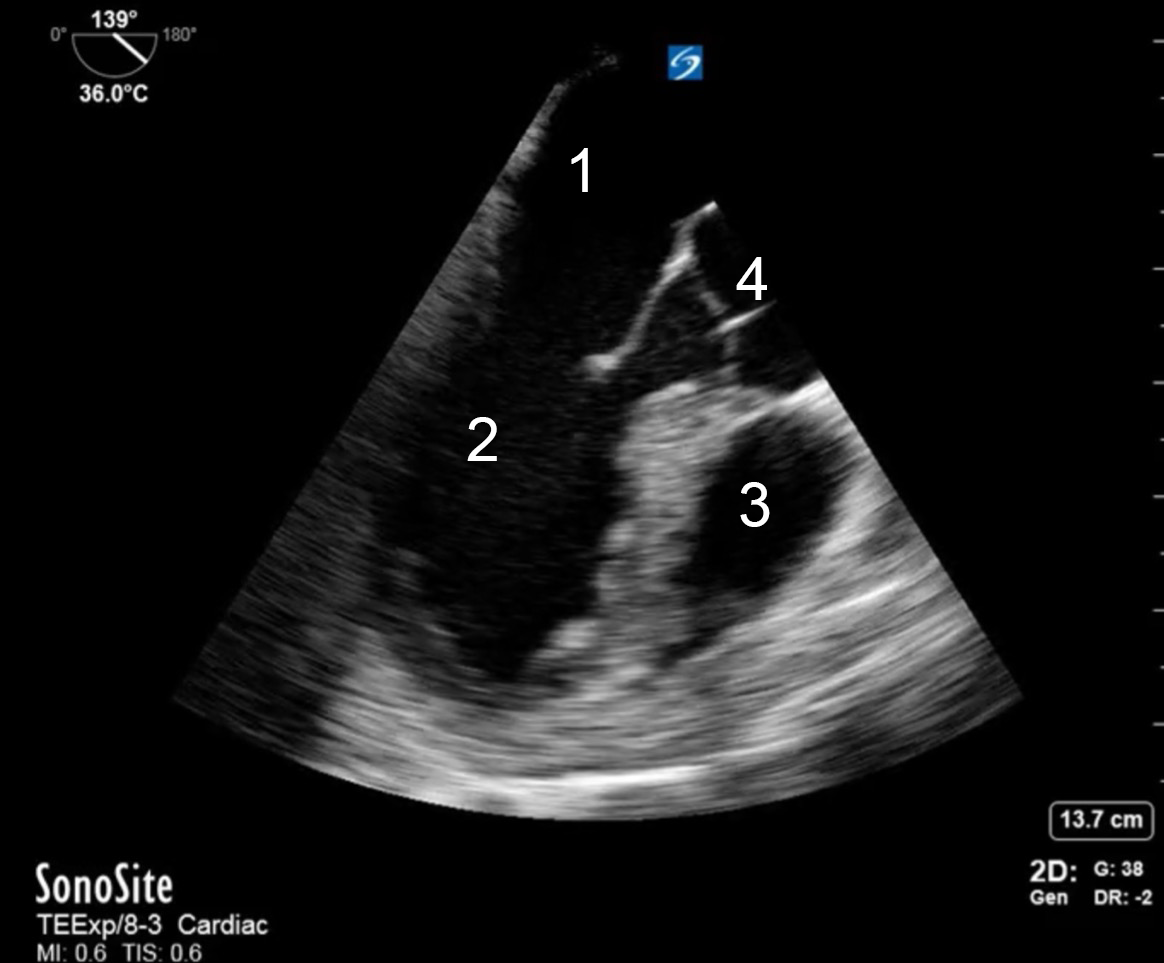

TEE Resus Mid-esophageal Long Axis Image

Left Atrium

Left Ventricle

Right Ventricle

Aorta